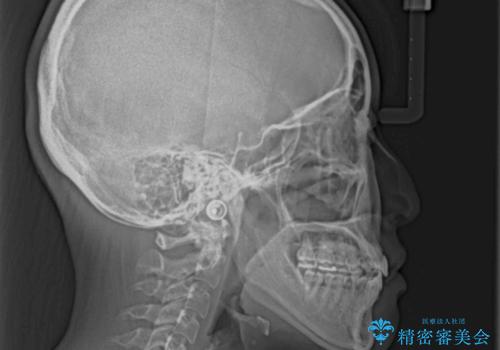

- 前歯のデコボコとクロスバイトを治したいとのことで来院された患者様です。

上下顎ともに歯列全体の側方拡大とIPR(歯と歯の間を削る)によってデコボコとクロスバイトが解消するように設計し、インビザラインにより治療を行うこととしました。

下顎骨の左側への骨格的なずれが強く、上下の正中の位置合わせや奥歯の咬み合わせ構築に苦労しました。